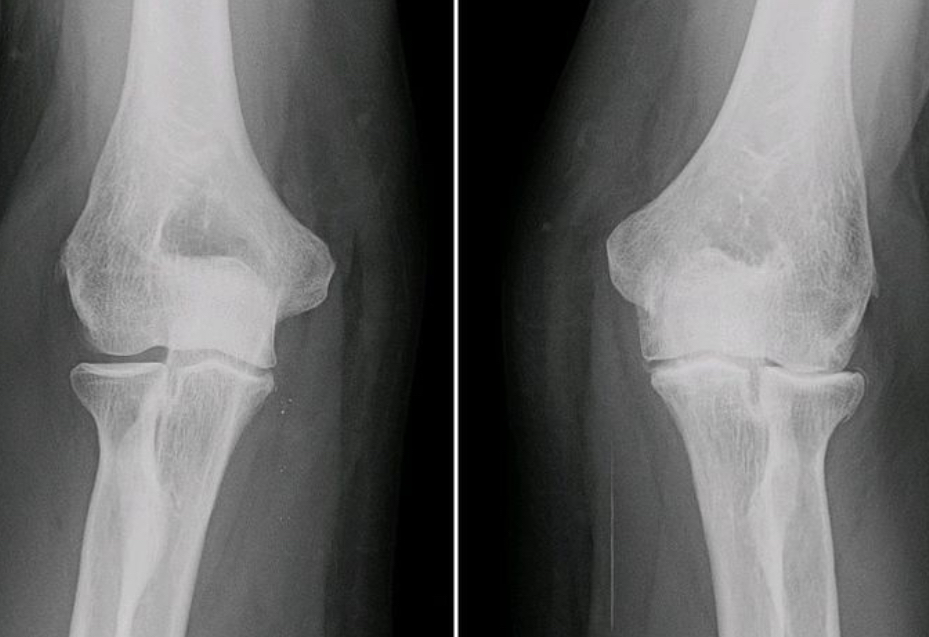

OA: What are the typical findings on x-ray?

Typical findings can be remembered with the mnemonic "LOSS":

Loss or narrowing of joint space due to thinning of cartilage

Osteophytes i.e. formation of new bony spurs at the joint margins

Subchondral sclerosis i.e. increased bone density beneath the cartilage

Subchondral cysts which are fluid-filled sacs in the subchondral bone